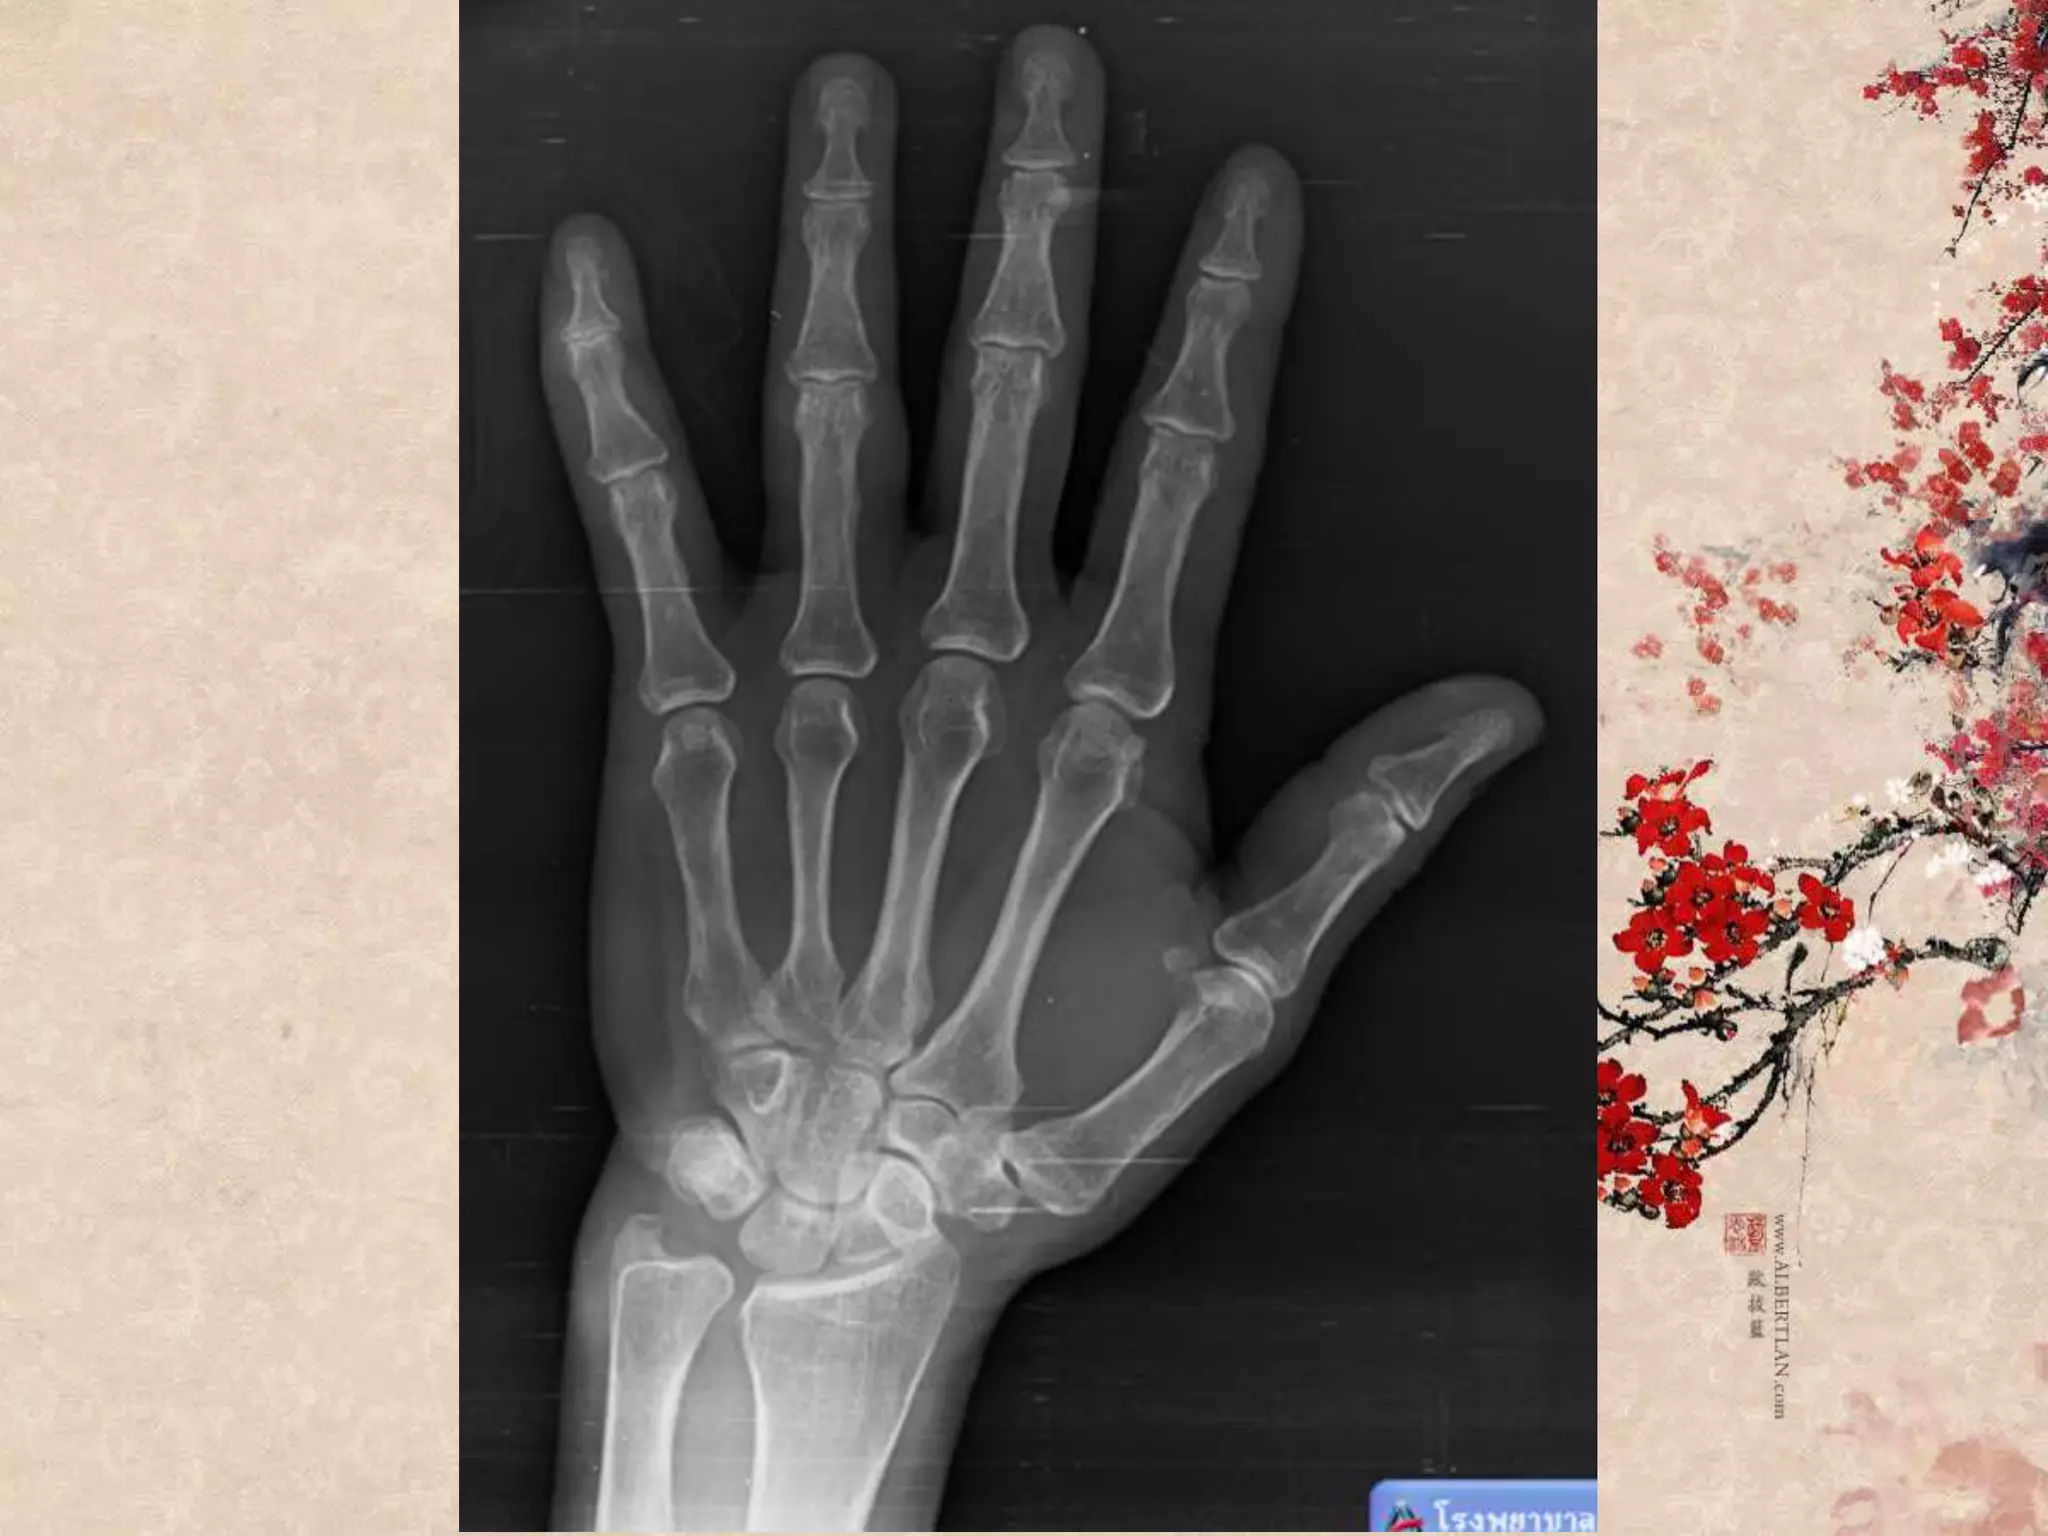

Patient profile หญิงไทย อายุ54 ปี Chief complaint รถจักรยานยนต์ล้มทับนิ้วมือซ้าย 2 ชั่วโมง ก่อนมาโรงพยาบาล

Primary survey A :can talk, no c-spine tenderness B : no dyspnea, RR 20 C : no active external bleeding full pulse, BP 102/80 D : E4V5M6 E : laceration wound 3 cm at Lt. ring finger, deep to bone

Secondary survey A :no drug/food allergy M : no medication P : no underlying disease L : last meal 4 hr E : รถจักรยานยนต์ที่จอดอยู่ ล้มทับนิ้วก้อยมือซ้าย มีแผลเปิด ปวดมาก ขยับนิ้วก้อยได้ ไม่ชาปลายนิ้ว มีเลือดออกซึมๆ เหตุเกิด 2 hr

Open Mallet finger

“Extensor tendon injury”